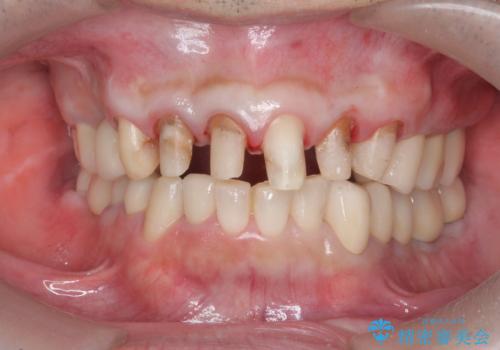

全ての歯を治療したい

- 「少しずつ色々な箇所が悪くなり、歯医者に通い続けている。全ての歯を長持ちするような状態にできるような治療を受けたい。」、と全顎・総合的な治療を希望され来院されました。

根管治療・矯正治療・歯周外科・セラミック補綴を含む様々な治療オプションを駆使し、長期間良好な状態に保てるような治療計画を立案します。

矯正治療を絡めた総合的な治療をお行なったことで、理想的な咬合関係を確立し安定した噛み合わせで仕上げることができました。

また歯周外科を行うことで歯ぐきの腫れを改善し、清掃性を高めています。